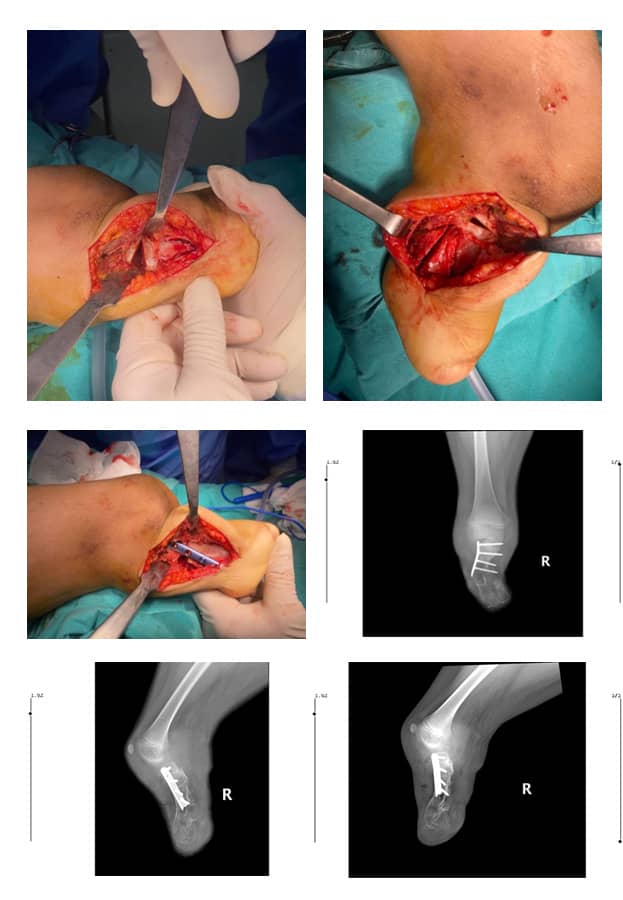

Операцията протече със запазване на пателарния сухожил и отстраняване на клиновидно-метатарзалната връзка, която притискаше кожата. По време на измерванията беше извършена отворена клиновидна остеотомия за корекция на деформацията в две равнини поради наличието на бизагитална деформация. Отстранената клиновидно-метатарзална връзка беше поставена в празната остеотомична зона за сливане, а фиксацията беше осъществена с плоча и винтове (Фиг. 9 А, В, С, D, E, F)

Фиг. 9

А: Отворена клиновидна остеотомия

B: Отстранен автотрансплантат от 4-ти метатарзал

C: Фиксация с плоча и винтове

D: Следоперативен антеропостериорен изглед

E: Следоперативен латерален изглед

F: Следоперативен кос изглед

В края на втория следоперативен месец пациентът нямаше болка и рентгеновото изследване показа сливане на костта на мястото на остеотомията (Фиг. 10 А, В).

Фиг. 10. След 2 месеца рентгеновото изследване показва сливане на костта на:

А. Латерален изглед

В. Антеропостериорен изглед